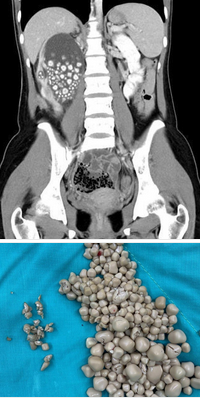

20‑летняя девушка из Тайваня почти год не пила воду — и оказалась на операционном столе.Вместо воды девушка употребляла бабл‑ти, соки и алкоголь. Последствия не заставили себя ждать: когда появились боли в спине, обследование (УЗИ) показало шокирующий результат — в одной почке обнаружили более 300 камней, отдельные из которых достигли размера 2 см.

Операция прошла успешно, но процесс удаления камней через трубку занял почти час. Теперь девушка строго следит за водным режимом и пьёт достаточное количество воды. Её история — серьёзное предупреждение всем, кто пренебрегает этим базовым правилом здорового образа жизни.